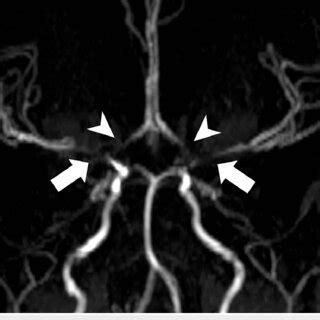

Mra circle of willis anatomy. .